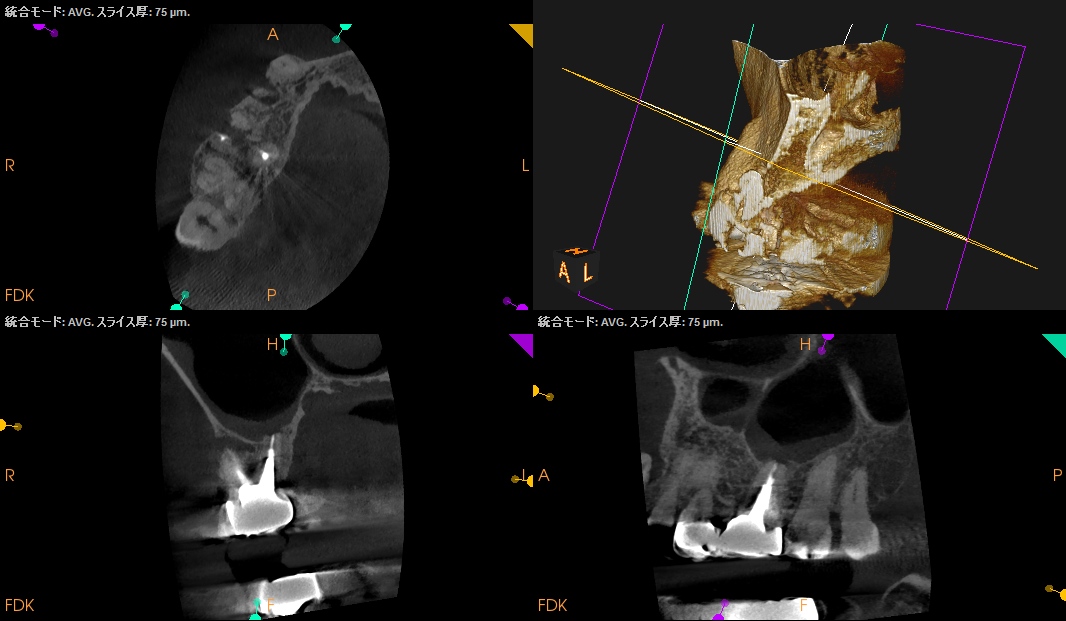

治療前の予測としては以下だ。

CEJよりも13mm先にApexがある。

が、この際にOsteotomyを行わなくてもApexには辿り着ける。

そしてApexから3mmで切断した時に、頬舌的には4.4mm削るだけで済む。

Very easyな外科治療だ。

そしてその際、Gutta PerchaがMBの中心にあることからこの根管は1根管であるということまでわかる。

まさにSuper easyなApicoectomyである。

このように

見れる・わかる・映りがいいCarestream社のようなCBCTがあれば, ここまで術前に予測ができるのである。